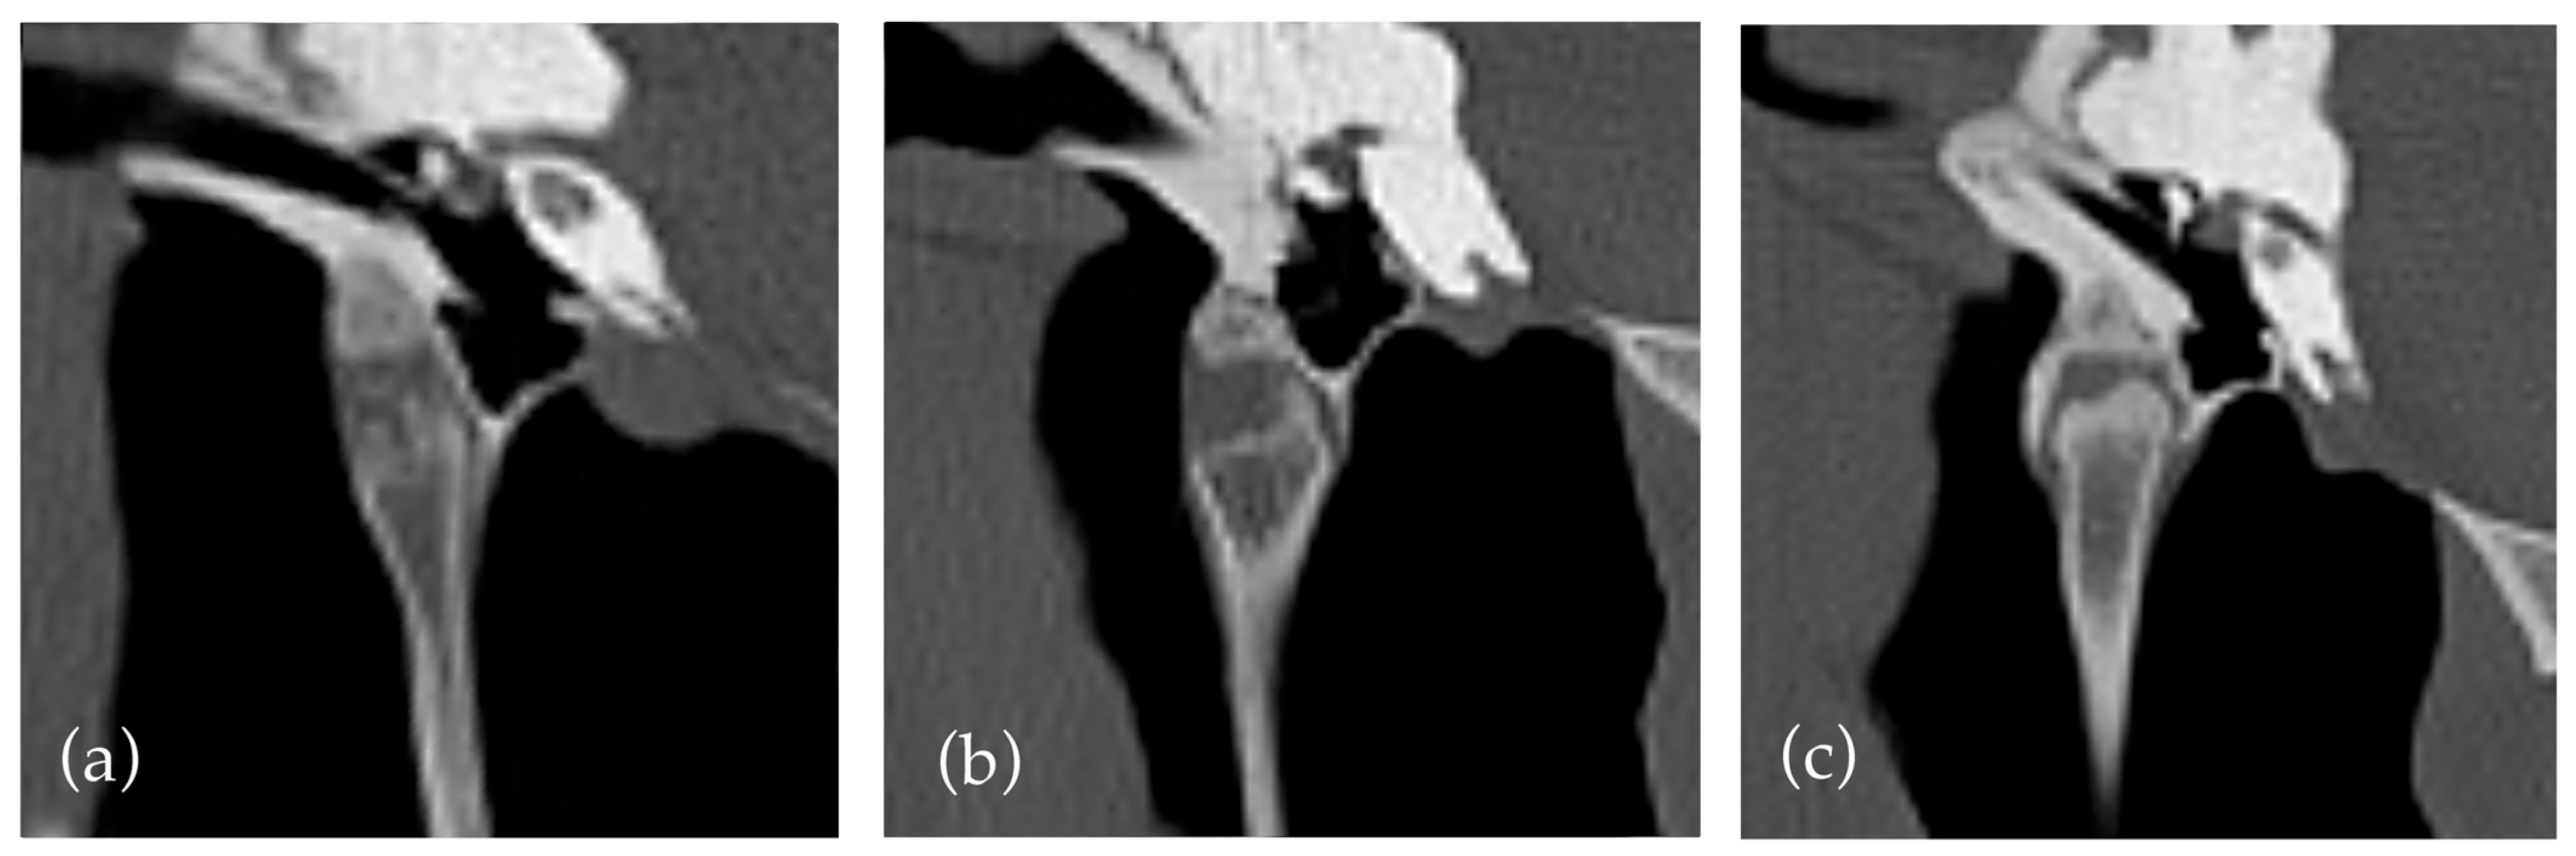

An existing grading system [17,21] was used to quantify new bone formation within the styloid sheath. The criteria were clarified that a grade two required new bone formation to cross the lateral and medial aspects of the joint. This decision was made due to a previous lack of clarity and the anatomy of the joint with a variably sloped medial aspect, which often affects the degree of new bone formation required to cross the joint. This is illustrated in Figure 1 where crossing new bone formation over the medial aspect of the joint can have limited relationship to the degree of new bone formation. The predisposition for medial distribution of new bone formation has been noted in previous papers [12]. The decision led to a relatively small number of horses with grade two changes (13) compared to grade one and three (157 and 26, respectively). This may suggest a limitation of the grading system to differentiate between mild and moderate cases, indicating a possible need to create a more even distribution between grades. Additionally, our interpretation classified horses as grade one if only medial new bone formation was present without extension around the joint, which may lead to underestimation/grading of some cases. The use of new bone formation crossing the joint is useful as it does not require measurement, but perhaps a grading based on the absolute rather than relative new bone formation may be more replicable and representative.

Figure 1. An illustration of the grades of temporohyoid joint. (a) Grade 0 shows no new bone formation. (bd) all show Grade 1 temporohyoid joints; however, they illustrate the variation within this grade; (b) shows new bone formation not crossing the joint, while (c,d) show different degrees of new bone formation both crossing the medial aspect of the joint. (e) Grade 2. (f) Grade 3.